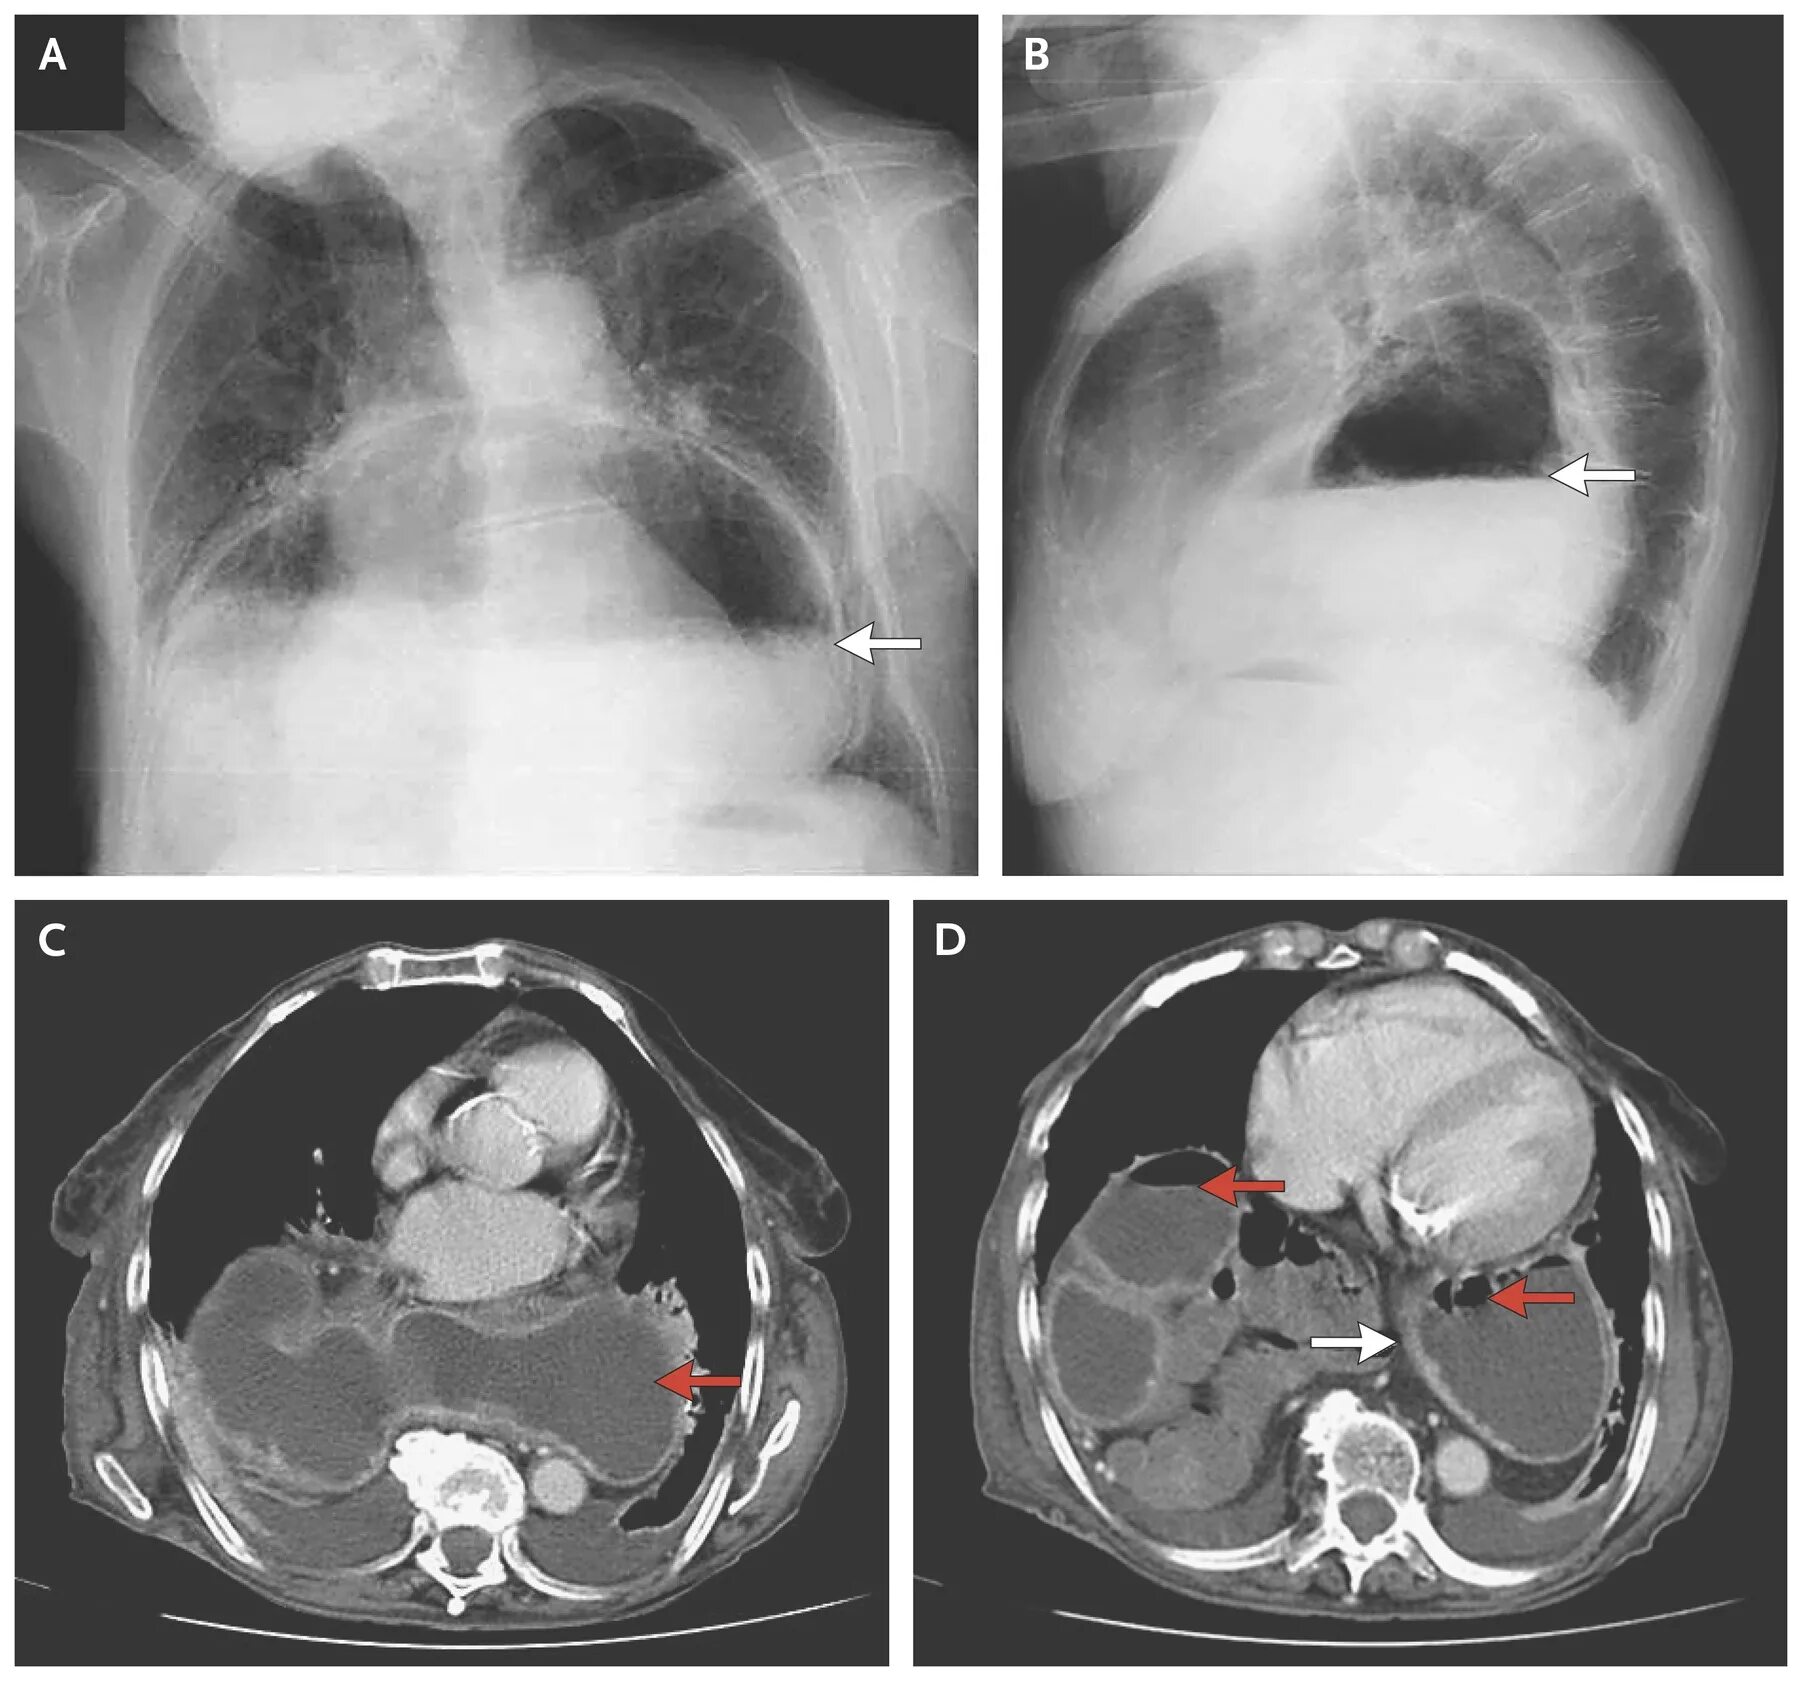

Как лечить диафрагму грыжу